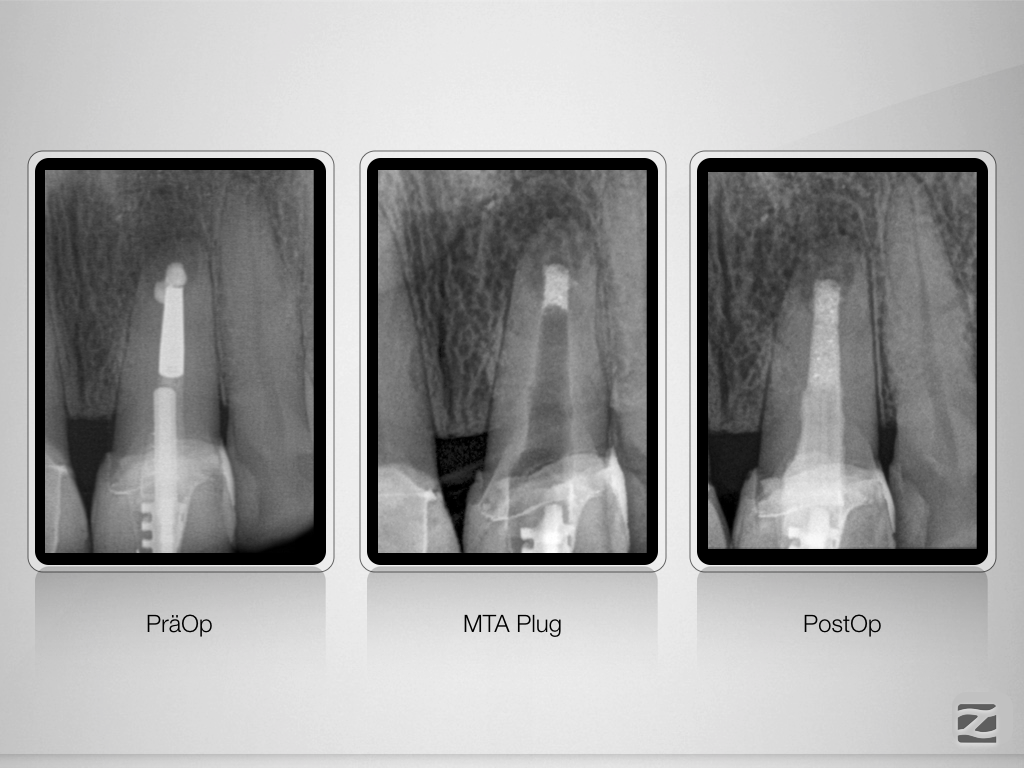

Hürdenlauf – Revision nach Resektion